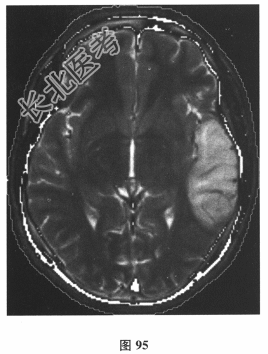

患者男,24岁。由于“反复发作性四肢抽搐3个月,言语困难1d”到院就诊。3个月前饮酒后出现四肢抽搐、意识丧失,持续3min左右自行缓解;10d前再发一次四肢抽搐。遂行颅脑CT(图94)及MRI平扫检查(图95)后予丙戊酸钠对症治疗。1d前再发四肢抽搐,出现言语困难。其母亲有糖尿病病史。查体:身材矮小,意识清楚,感觉性失语,四肢肌力、肌张力正常,腱反射对称活跃,深、浅感觉正常,病理反射未引出,脑膜刺激征(-)。脑脊液:压力110mmH₂O,细胞、蛋白、葡萄糖、氯化物均正常,乳酸3.6mmol/L↑。